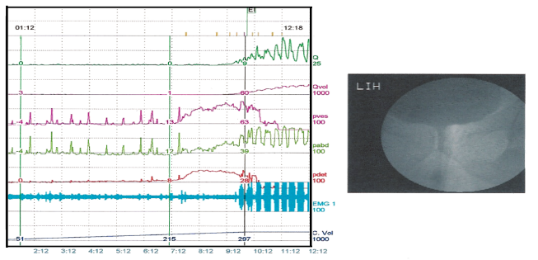

● 錄影尿路動力學檢查

薦神經刺激器植入治療排尿困難、高濃度血小板膀胱注射,研究其是否對於膀胱表皮具有修復作用等。